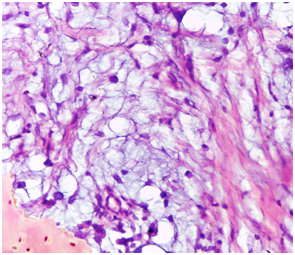

Histologically, the overlying epithelium displayed signs of pseudoepitheliomatous hyperplasia. The connective tissue revealed an impressive myxomatous background, in which lobules of myxoid areas were conspicuous (Figure 2). Evident in the histological field was the occasional peripheral bone formation, which embraced the myxomatous stroma (Figure 3). The focally rich fibrocellualrity of the lesion should neither mitotic figures nor cellular atypia. Neither granuloma formation nor malignant features could be appreciated (Figure 4). The diagnosis was, accordingly, an ossifying fibromyxoid tumor. Regarding confirming the diagnosis of OFMT, no immunohistochemical markers were indicated because no specific markers are adjunctively recruited in the medical literature. A follow-up interval was determined: every 6 months. The patient was educated about the necessity of compliance.

Figure 2 Photomicrograph showing signs of pseudoepitheliomatous hyperplastic epithelium, overlying an impressive myxomatous background. (H&E stained, Original magnification: 4x).